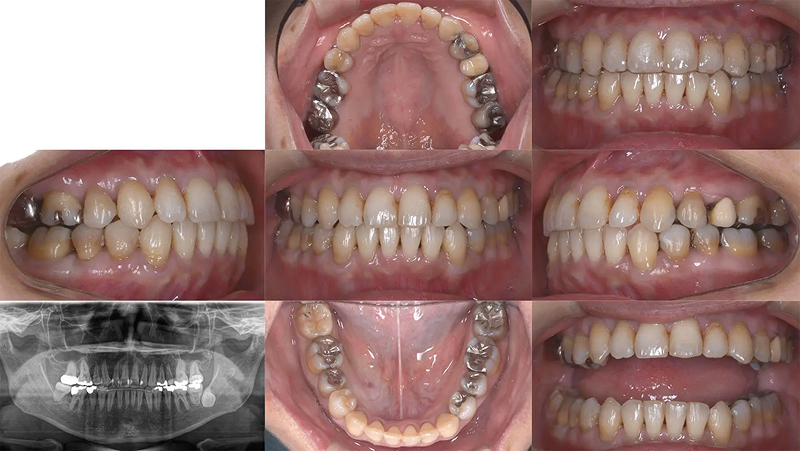

Case02前歯の凸凹を改善した症例

結婚式前に前歯の凸凹を治したいといらっしゃいました。叢生は軽度でタイムリミットは8か月でした。診査の結果、非抜歯なら十分に間に合うと診断しました。上下顎ともに少し側方拡大を行い、歯を並べました。2年後、問題なく経過しています。

初診 2017.3.23

矯正開始 2017.3.24

ファイナル 2017.10.27

治療2年後 2019.10.12

| 主訴 | 前歯の凸凹が気になる |

|---|---|

| 診断 | 両側アングル1級叢生 |

| 矯正方法 | オーバーレイアーチを併用したマルチブラケット |

| 矯正期間 | 7か月・9回 |

| 費用 | 690,000円(税別) |

| 調整料 | 月1回 5,000円(税別) |